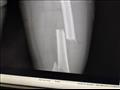

أوضح عم الطالبة أنه بعد توجهه إلى مستشفى كفر الشيخ العام، حيث نُقلت ابنة شقيقه، سأل زميلتها فاكتشف أن أحد الشابين على التروسيكل كان يتحرش بهما، قبل أن يصدم المجني عليها، محدثًا إصابتها بكسر مضاعف في الفخذ، وجرح قطعي بالعين، وكدمات وسحجات في أنحاء متفرقة من الجسد.

لفت عم الطالبة أيضًا إلى أن الأطباء أكدوا ضرورة خضوع ابنة شقيقه لجراحة تستلزمها حالتها لزراعة مسمار نخاعي يمر بثلاث عظام مكسورة بفخذها.